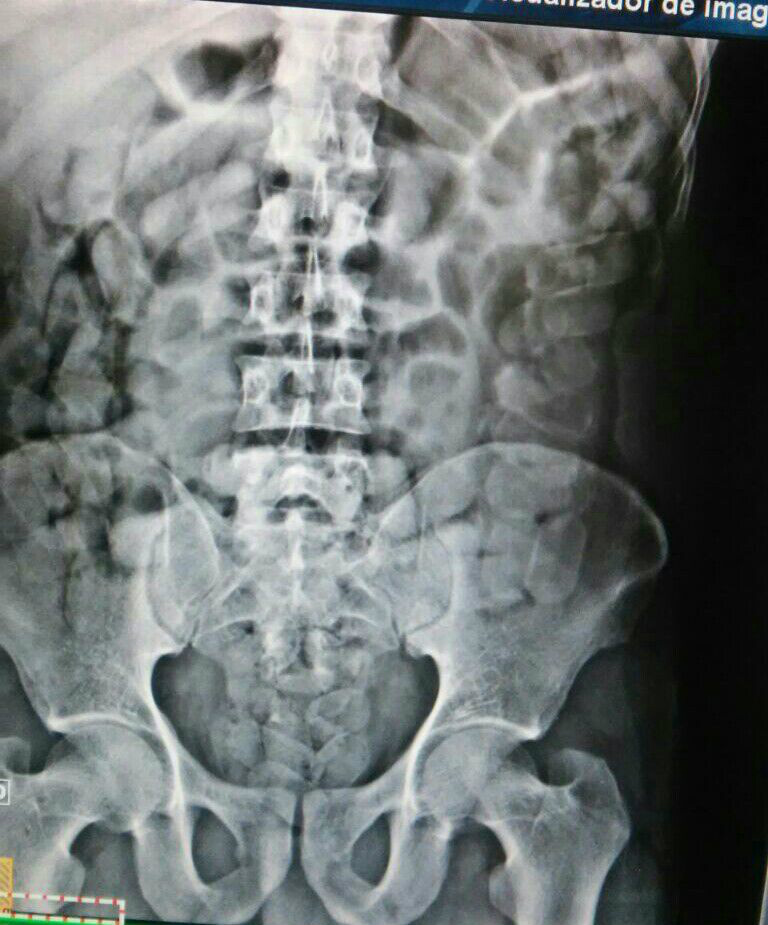

Os suspeitos identificados como Miguel Antônio Geremias (50) de Cuiapora (PR) e Manuel Elio Tomicha Yopie (32 ), boliviano não souberam explicar o porque da fuga sendo assim detidos, Manuel foi encaminhado ao Hospital Auxiliadora , onde após R-X foi constatado a cocaína em seu estômago.

Questionado da procedência da droga Manuel confessou ter ingerido a droga -52 cápsulas totalizando aproximadamente 650gr de cocaína- na cidade de Corumbá (MS) para entrega la a Ilton Gomes dos Santos.

52 cápsulas totalizando aproximadamente 650gr de cocaína (Foto Rádio Caçula)